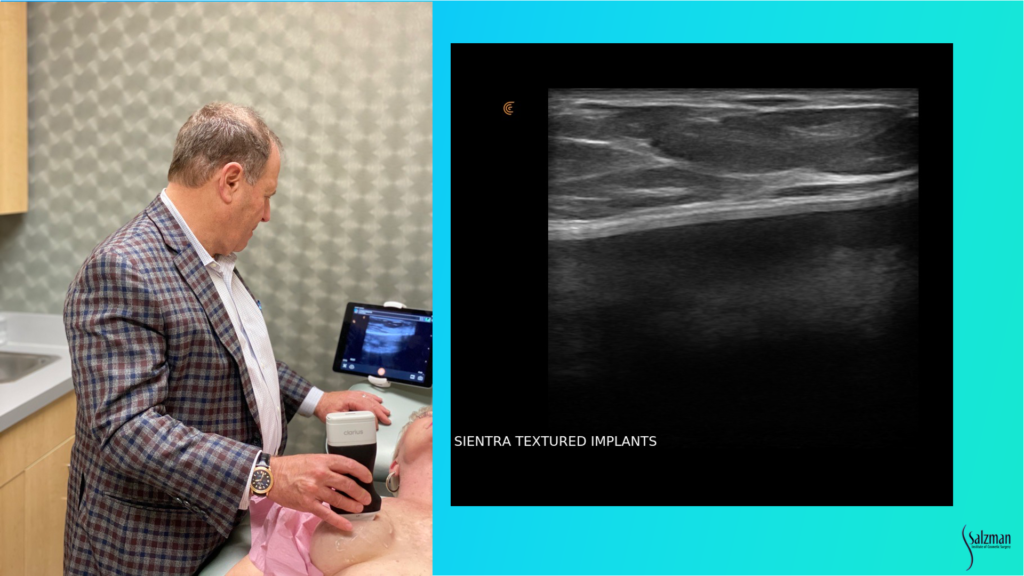

Setting Up for the Exam

This is my setup in a regular exam room. I’m using the new Clarius L7 HD device with an iPad. I bought a bracket online for under $100 and hooked it to the back of the chair so that I can touch the screen if I need to. But I usually use the buttons on the device instead of touching the screen. I’ve programmed the bottom button to freeze the image and the top button to save the image. To record a video, I push the bottom button and a little icon appears that looks like a movie camera – it will take a 10-second video and stores it on the iPad and then upload it to the Cloud at the end of the exam. It’s very simple to do from the room.

Recognizing a Normal Textured Breast Implant

When looking for pathology, we have to know what normal looks like. This is a Sientra textured implant. You can see the breast parenchyma up above where it says breast, so it’s skin, a little bit of subcutaneous fat and then the dense white breast parenchymal tissue with those little striations, which are the support structures. And then the white line that’s just underneath the parenchyma, or under the muscle if it’s a submuscular implant, is the capsule. Usually, the implant shell is a bilaminar structure. And when you look in really high definition, sometimes it will look like it has three different lines, with the fourth line being the capsule that’s just above. That’s a normal, unbroken implant.